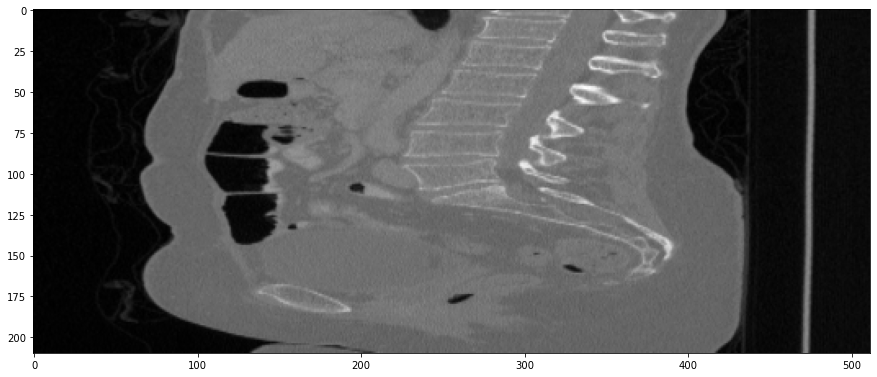

Refer to caption

(a) True Thick-slice image

(b) Simple Averaging

RMSE: 0.0357, PSNR: 34.9781

(c) Gaussian Averaging

RMSE: 0.0454, PSNR: 32.8866

(d) Direct Downsampling

RMSE: 0.0486, PSNR: 32.2861

(e) Proposed Simulation

RMSE: 0.0070, PSNR: 49.1774

Figure 4: Sagittal-plane thick-slice image quality comparison across four simulation methods.